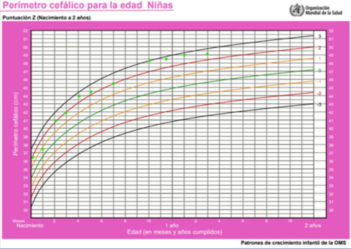

El crecimiento en peso, longitud y perímetro craneano según la edad se muestran en las (Figura 1), (Figura 2) y (Figura 3). En la (Figura 4) se muestra la evolución del peso de acuerdo a la longitud.

Figura 3: Gráfica de perímetro cefálico de acuerdo a la edad. Los puntos verdes indican los valores para esta paciente de acuerdo a la edad.

La antropometría en el momento de la consulta evidenció: peso de 8 kg (score Z del índice antropométrico peso para la edad -1,7); longitud de 68 cm (score Z de longitud para la edad -3,3). La relación peso/longitud tenía un score Z de 0,27. El perímetro cefálico era de 47 cm (score Z 0,55).

Otro elemento importante a analizar son las proporciones corporales que incluyen: perímetro craneano; envergadura o distancia entre la punta de los dedos medios de las manos; medición del segmento corporal inferior o distancia entre la sínfisis púbica y la planta de los pies; y el segmento corporal superior, que se calcula de la diferencia entre talla y segmento inferior, o a través de la medición de talla sentado6. La proporción entre segmento superior y segmento inferior del cuerpo normalmente declina con la edad, alcanzando aproximadamente 1,7 en recién nacidos y 1 desde los 10 años hasta la vida adulta2,5. En esta paciente se diagnosticó una alteración en estas proporciones, con perímetro craneano proporcionalmente elevado y alteración de la relación entre los segmentos corporales.